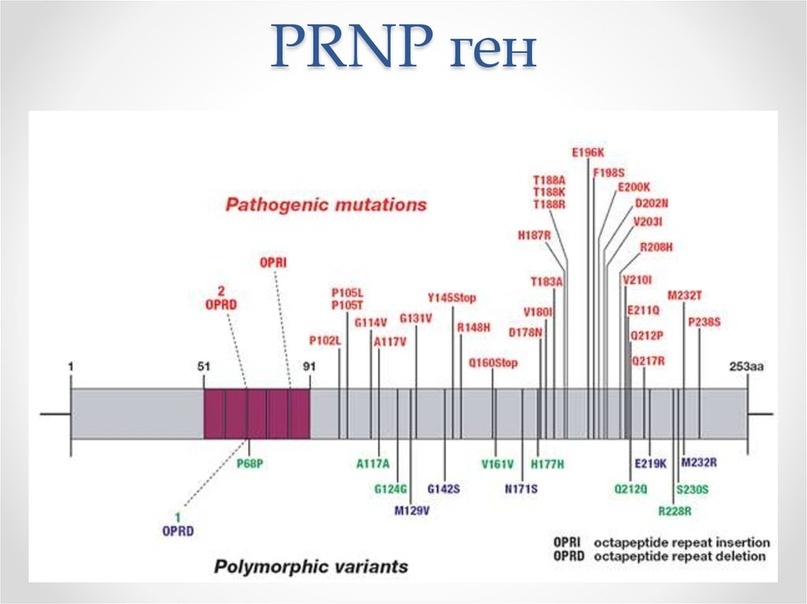

Ген PRNP, кодирующий PrP, обладает высокой степенью консервативности. Несмотря на это, в настоящее время установлены около сорока различных мутаций этого гена, которые связаны с различными прионными болезнями. В ряде случаев превращение нормального белка в прионный связано с мутациями этого гена. К таким заболеваниям относятся спорадичекая форма болезни Кройтцфельдта-Якоба, синдром Герстманна-Штреусслера-Шейнкера и фатальная семейная бессонница. Особую роль в этом имеют полиморфизм кодона 129, кодирующий метионин либо валин.

Среди заболевших болезнью Кройтцфельда-Якоба преобладают индивиды, гомозиготные по метионину либо валину, что позволяет предположить «защиту» от заболевания при гетерозиготности кодона 129. Было высказано предположение, что на агрегацию и конформационные изменения молекул PrP влияет аминокислота этого кодона. Эти данные получены на основании исследования членов племени форе.

Развитие болезни может происходить как за счёт точечных мутаций, так и в результате рекомбинантных событий. Мутации гена, кодирующего PrPС, программирует выработку другой, мутированной плоской формы – PrPSc с изменёнными аминокислотами. Таким образом, образование инфекционных прионовых белков происходит не за счёт репродукции молекулы PrPSc, попавшей в организм, а за счёт синтеза новых молекул, кодируемых мутировавшим геном PrPС.